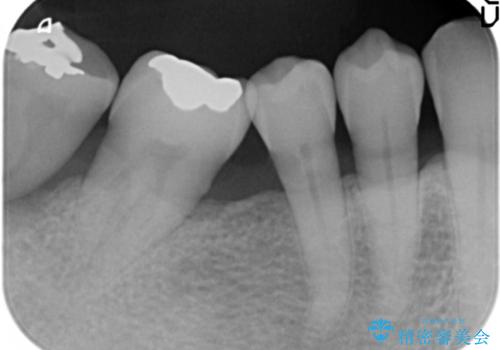

60代男性 奥歯のブリッジ 倒れこんでいる奥歯を部分矯正

- 右下の親知らずが咬むと痛いとのことでした。

親知らずを抜いて、倒れこんでいる手前の歯を矯正治療で移動させ、ブリッジにしました。

矯正治療をしなければ、倒れこんでいる影響で手前の奥歯も含めて歯周病で悪化してしまうため、しっかり起こして治療をしました。